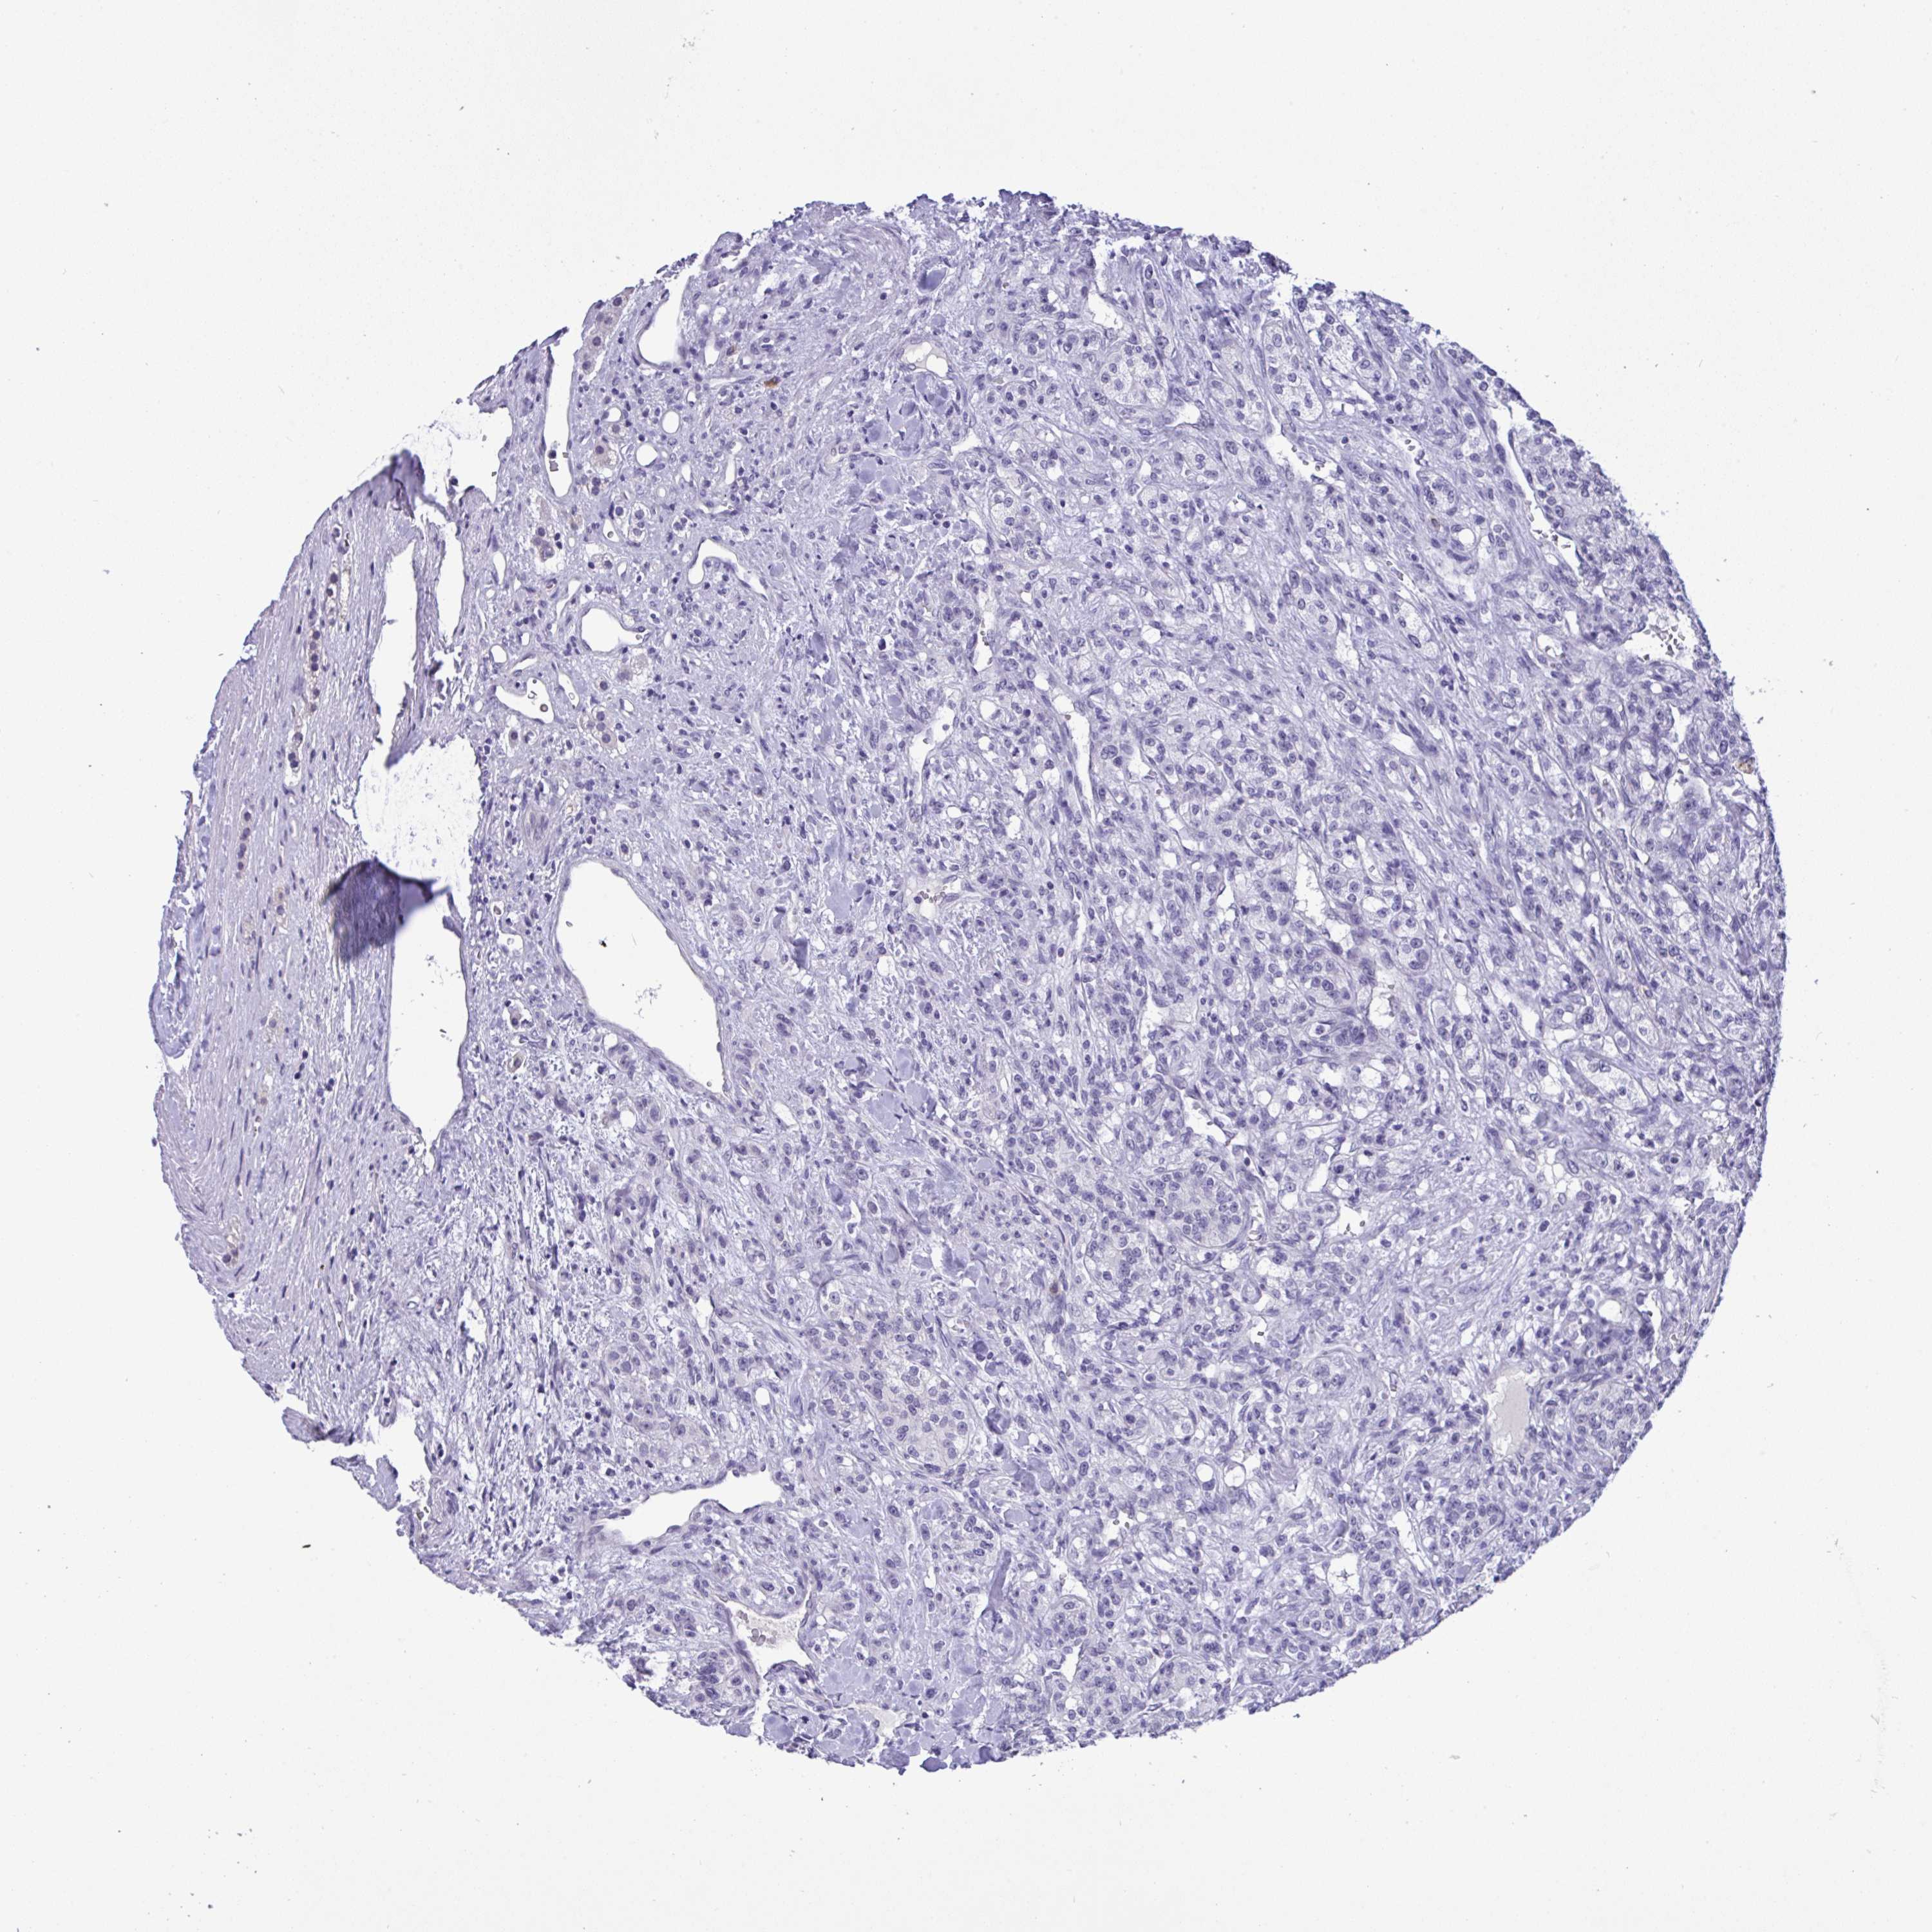

Renal cancer

Kidney chromophobe

KIDNEY CHROMOPHOBE (TCGA) - Interactive survival scatter ploti

The Survival Scatter plot shows the clinical status (i.e. dead or alive) for all individuals in the patient cohort, based on the same data that underlies the corresponding Kaplan-Meier plots. Patients that are alive at last time for follow-up are shown in blue and patients who have died during the study are shown in red.

The x-axis shows the expression levels (FPKM) of the investigated gene in the tumor tissue at the time of diagnosis. The y-axis shows the follow-up time after diagnosis (years). Both axes are complimented with kernel density curves demonstrating the data density over the axes. The top density plot shows the expression levels (FPKM) distribution among dead (red) and alive patients (blue). The right density plot shows the data density of the survived years of dead patients with high and low expression levels respectively, stratified using the cutoff indicated by the vertical dashed line through the Survival Scatter plot. This cutoff is automatically defined based on the FPKM cutoff that minimizes the p-score. The cutoff can be changed by dragging the vertical line or by entering a cutoff value in the square labeled "Current cut-off".

Under the Survival Scatter plot the p-score landscape (black curve; left axis) is shown together with dead median separation (red curve; right axis). Dead median separation is the difference in median mRNA expression between patients who have died with high and low expression, respectively. It is calculated as follows: median FPKM expression of dead patients with high expression - median FPKM expression of dead patients with low expression. This is intended to aid the user in visually exploring custom cutoffs and the associated p-scores and dead median separation.

Individual patient data is displayed and can be filtered by clicking on one or more of the category buttons on the top of the page. Categories describing expression level and patient information include: high, low, alive, dead, female, male and tumor stages. The scale of the x-axis can be toggled between linear and log-scale by clicking on the "x log" button. Mouse-over function shows TCGA ID, patient information and mRNA expression (FPKM) for each patient.

& Survival analysisi

Kaplan-Meier plots summarize results from analysis of correlation between mRNA expression level and patient survival. Patients were divided based on level of expression into one of the two groups "low" (under cut off) or "high" (over cut off). X-axis shows time for survival (years) and y-axis shows the probability of survival, where 1.0 corresponds to 100 percent.

YBX2 is not prognostic in Kidney Chromophobe (TCGA)

TCGA RNA samplesi

RNA-seq data is reported as average FPKM (number Fragments Per Kilobase of exon per Million reads), generated by the The Cancer Genome Atlas (TCGA) .

Normal distribution across the dataset is visualized with box plots, shown as median and 25th and 75th percentiles. Points are displayed as outliers if they are above or below 1.5 times the interquartile range. FPKM values of the individual samples are presented next to the box plot.

Average pTPM 4.0

Number of samples 64